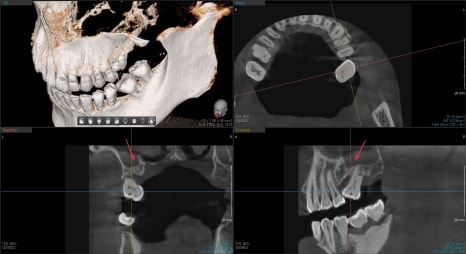

수술 전후 3D CT를 통해 잘 되었는지 평가를 했습니다.

수술 전 비어있던 상악동 공간이

수술 후 흰색으로 표현된 임플란트 주변이 뼈이식재가 주변을 잘 감싸고 있는 것을 볼 수 있습니다.